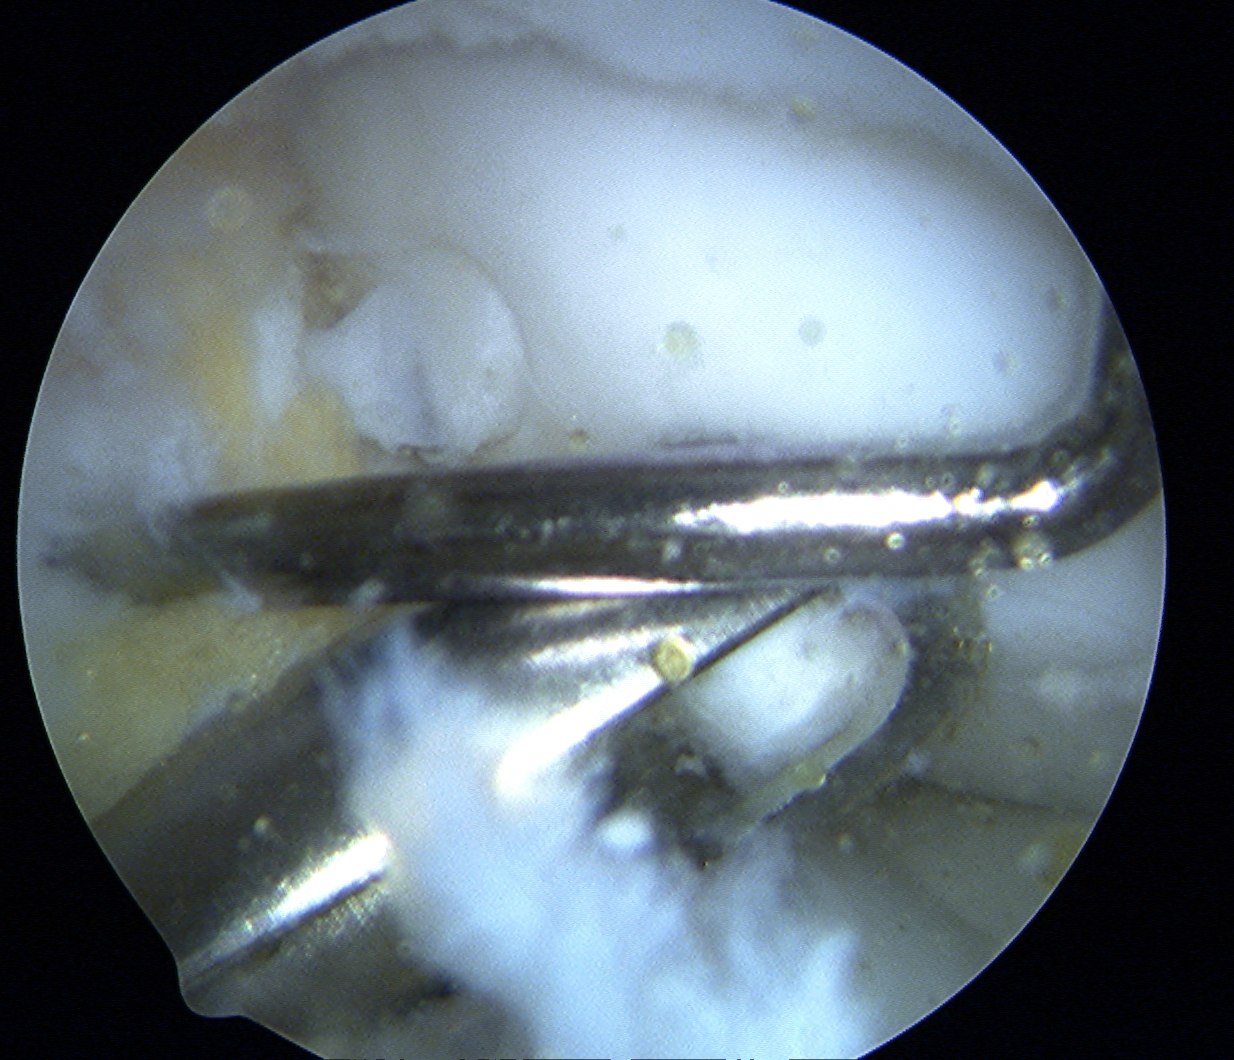

Insert dilator

Insertion device

- place over drill hole

- impact with hammer to seat in cartilage

- insert plug

- use tap to insert plug

- best to countersink 1 - 2 mm